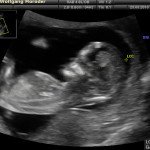

L’ecografia è una tecnica che consente di vedere gli organi del nostro corpo con l’utilizzo di onde sonore ad alta frequenza (ultrasuoni, non udibili dall’orecchio umano) che attraversano i tessuti. La sonda ecografica invia impulsi di onde sonore nel corpo. Quando le onde sonore arrivano al feto mandano degli echi: tali echi (o onde di ritorno) sono trasformati in immagini sul monitor dell’ecografo. Con l’ecografia è quindi possibile osservare in modo dettagliato il feto.

- Perché fare l’ecografia in gravidanza?

Le ragioni più comuni per cui si esegue una ecografia in gravidanza sono: determinare il numero degli embrioni o dei feti, visualizzare l’attività cardiaca fetale, determinare l’epoca di gravidanza, valutare l’anatomia e la crescita fetale, determinare la posizione del feto e della placenta

- Che cosa si vede con l’ecografia?

Nei primi mesi di gravidanza, con la misura della lunghezza del feto, è possibile valutare se lo sviluppo corrisponde all’epoca di gravidanza valutata in base alla data dell’ultima mestruazione, il numero dei feti e la presenza dell’attività cardiaca.

Dal secondo trimestre si misurano altre parti fetali, ed i valori di tali misure vengono confrontati con quelli delle curve di riferimento. Si può così valutare la normalità o meno della crescita fetale. Inoltre periodo si visualizzano la sede di inserzione placentare e la quantità di liquido amniotico.

- E’ possibile rilevare con l’ecografia anomalie fetali maggiori?

La possibilità di rilevare un’anomalia maggiore dipende dalla sua entità, dalla posizione del feto in utero, dalla quantità di liquido amniotico e dallo spessore della parete addominale materna; perciò è possibile che talune anomalie fetali possano non essere rilevate all’esame ecografico. Inoltre alcune malformazioni si manifestano tardivamente (al 7°- 9° mese) e perciò non sono visualizzabili in esami precoci. L’esperienza finora acquisita suggerisce che un esame ecografico routinario, non mirato, consente di identificare dal 30 al 70% delle malformazioni maggiori. Non è compito dell’ecografia la rilevazione delle cosiddette anomalie minori (Linee Guida SIEOG 2006).

- L’ecografia è innocua per il feto?

Gli ultrasuoni sono utilizzati nella pratica ostetrica da oltre 40 anni e non sono stati riportati effetti dannosi, anche a lungo termine, sul feto. Per tale ragione, con le procedure oggi adottate, l’uso diagnostico dell’ecografia è ritenuto esente da rischi. Ovviamente, come in tutte le cose, è bene non eccedere oltre la necessità facendo frequenti esami non necessari.